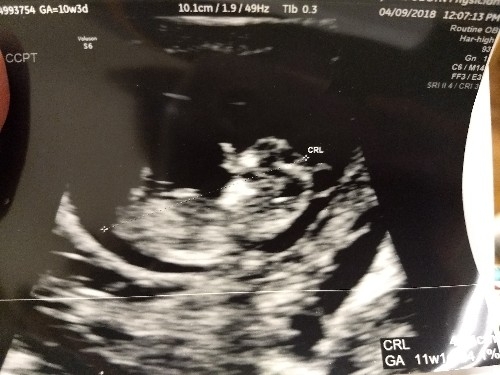

• I had my first ultrasound on Monday! I'm not as far along as I thought - I thought I was past 10 weeks but I'll be just 10 weeks tomorrow. So glad I decided to have an early ultrasound - last pregnancy I just had one at 20 weeks. This time around I was having cramping and bleeding and something seemed off. I guess this is why!!!! Seeing double!! They think identical but can't quite be certain yet as I only wanted an abdominal ultrasound this visit. Needless to say I'm freaking out! New due date of November 8th instead of the 3rd...but I'm sure with twins it may be October!

Holy cow, identical twins!! Congratulations! The hospitals I've worked at deliver identical twins no later than 36 weeks (which I believe is the recommendation) due to the increased risks if you go past that. FX for a smooth pregnancy for you!